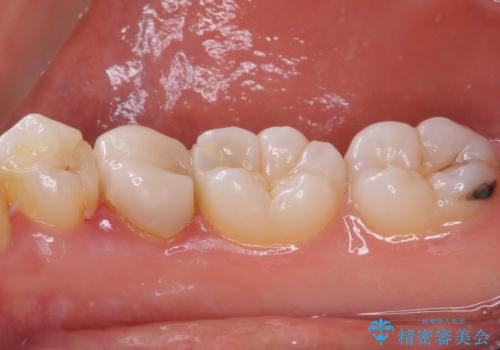

- 神経を抜く処置の後に装着したプラスチックのクラウンが外れてしまったとのことで来院された患者様です。

患者様自身、神経の取り除かれた歯はしっかりと製作されたクラウンを装着するべきと理解していただいていたため、オールセラミッククラウンにて補綴治療することとしました。

丈夫なクラウンを装着できただけでなく、形態や色調も自然に仕上げることができました。